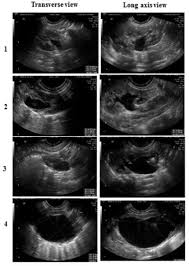

Kidney Stone Pregnancy Ultrasound. Extra corporeal shock wave lithotripsy eswl this method of high ultrasound waves for fragmenting kidney stones is highly contraindicated during pregnancy due to its harmful effect. However the drawback of undergoing a renal ultrasound is that it cannot identify certain types of kidney stones and may not be able to identify the cause of an enlarged kidney whether it is due to pregnancy or due to the obstruction caused by a kidney stone.

However the drawback of undergoing a renal ultrasound is that it cannot identify certain types of kidney stones and may not be able to identify the cause of an enlarged kidney whether it is due to pregnancy or due to the obstruction caused by a kidney stone. Kidney stone diagnosis during pregnancy remains challenging and ultrasound is currently still considered the first line imaging modality in this group of patients but its sensitivity is only 34 and often additional imaging is needed. Statistics say that about 10 percent of women will have a stone during their lifetime.